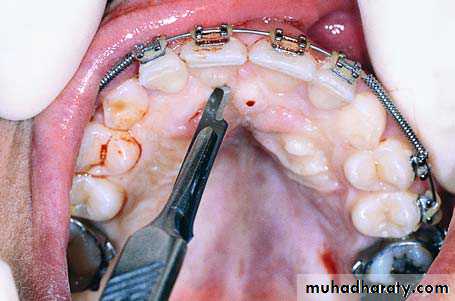

Palatal incision along the cervical lines of teeth using a scalpel with a no. 15 blade

Reflection of the mucoperiosteal flap. Arrow points to the nasopalatine nerve